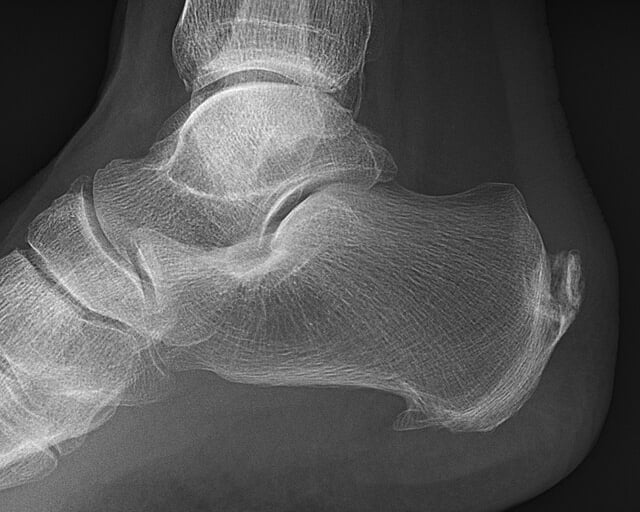

A veces se encuentra mediante radiografía un espolón calcáneo, que es un pico que se forma en la inserción de la fascia plantar. A primera vista parece un elemento dañino y que se puede clavar en la planta del pie, ya que esto coincidiría con el dolor tipo punzante de la fascitis. Aunque no necesariamente es algo malo.

Cuando existe un proceso inflamatorio o degenerativo como es el caso de la fascitis plantar, pueden generarse depósitos de calcio en la inserción de la fascia como un intento de adaptación de la zona. De hecho, por su forma y disposición, es espolón no se clava en ningún sitio, sino que sufre fuerzas de tensión.

No sólo eso, sino que se ha demostrado que a mayor tamaño del espolón, menores niveles de dolor tiene la persona.